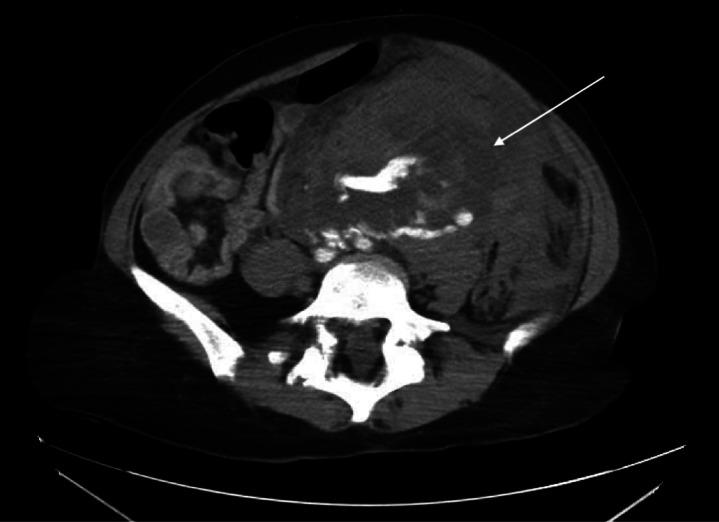

We present a case of a woman with a prior history of ovarian cyst presenting with a ruptured renal artery aneurysm. Prompt computed tomography (CT) imaging revealed a left renal artery aneurysm rupture with hemoperitoneum and renal infarct. She underwent emergency laparotomy and nephrectomy and was ultimately discharged in good condition.

我们报告一例有卵巢囊肿病史的女性出现肾动脉动脉瘤破裂的病例。及时的计算机断层扫描(CT)成像显示左肾动脉动脉瘤破裂伴腹腔积血和肾梗死。她接受了紧急剖腹手术和肾切除术,最终康复出院。